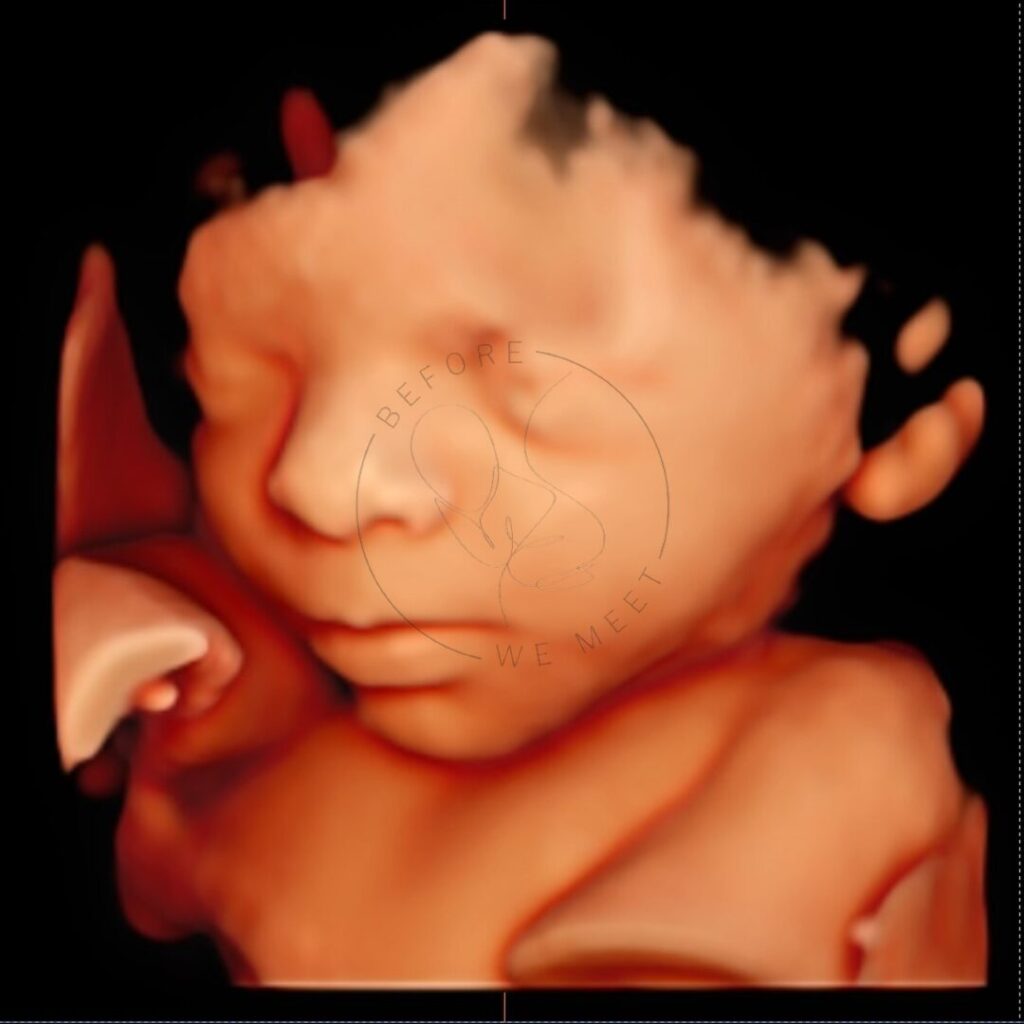

Veel ouders kiezen voor een pretecho als herinnering aan de zwangerschap of om samen met familie of vrienden extra naar de baby te kijken. Bij een 3D- of 4D-echo zien we duidelijk het gezichtje in kleur en zien we soms een lachje of een gaapje!

Een 3D/4D echo is éxtra bijzonder doordat we de baby met al zijn of haar details kunnen zien in stilstaande en bewegende beelden. Op wie lijkt zijn/haar neusje? Heeft hij/zij al bolle wangetjes? Of misschien zien we de baby zelfs wel drinken of lachen? Het laat jou (en ons!) verwonderen hoe magisch het nieuwe leven dat in je buik groeit is!

Iedere periode van de zwangerschap vinden wij even bijzonder, juist omdat je per maand zoveel verschil kunt zien. Echter is herkenning van het gezichtje het mooiste tussen de 24e en 30e week van de zwangerschap en afhankelijk van hoe de baby in je buik ligt, of hij/zij zich verstopt achter handjes, voetjes of de placenta en hoeveel vruchtwater er aanwezig is. Mocht het daardoor niet lukken om de baby goed in beeld te krijgen dan mag je nogmaals kosteloos terugkomen voor een echo van 20 minuten.